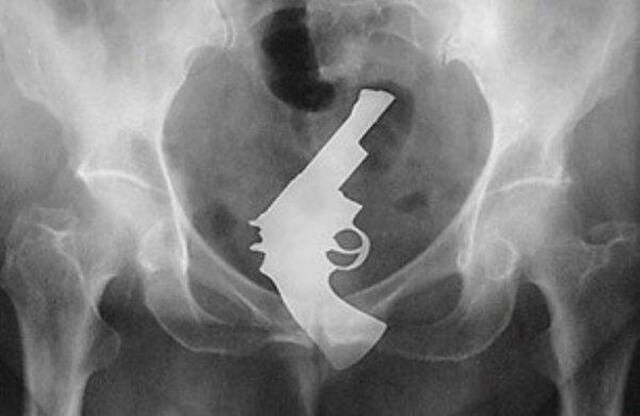

Röntgen Filminde İnsanların İçinden Çıkan Acayip Maddeler

1 / 9